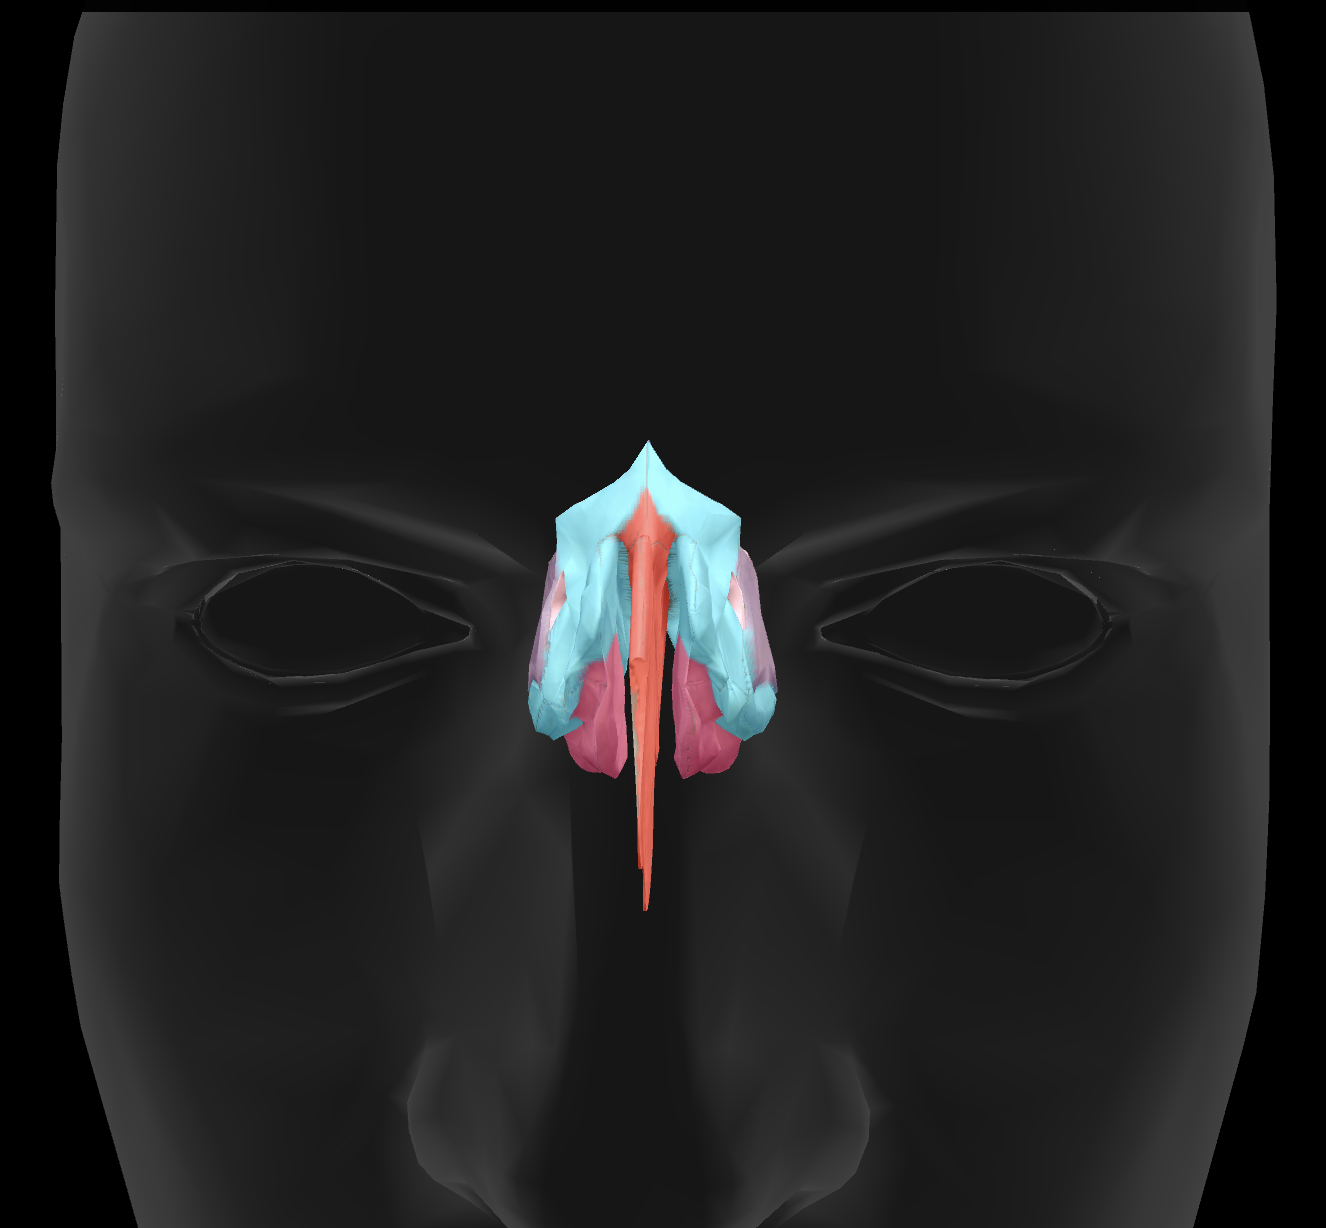

What features make up the nasal septum?

perpendicular plate of ethmoid bone and vomer

What is the name of this feature?

perpendicular plate

What is the name of this feature?

middle nasal conchae

What is the name of this feature?

superior nasal conchae